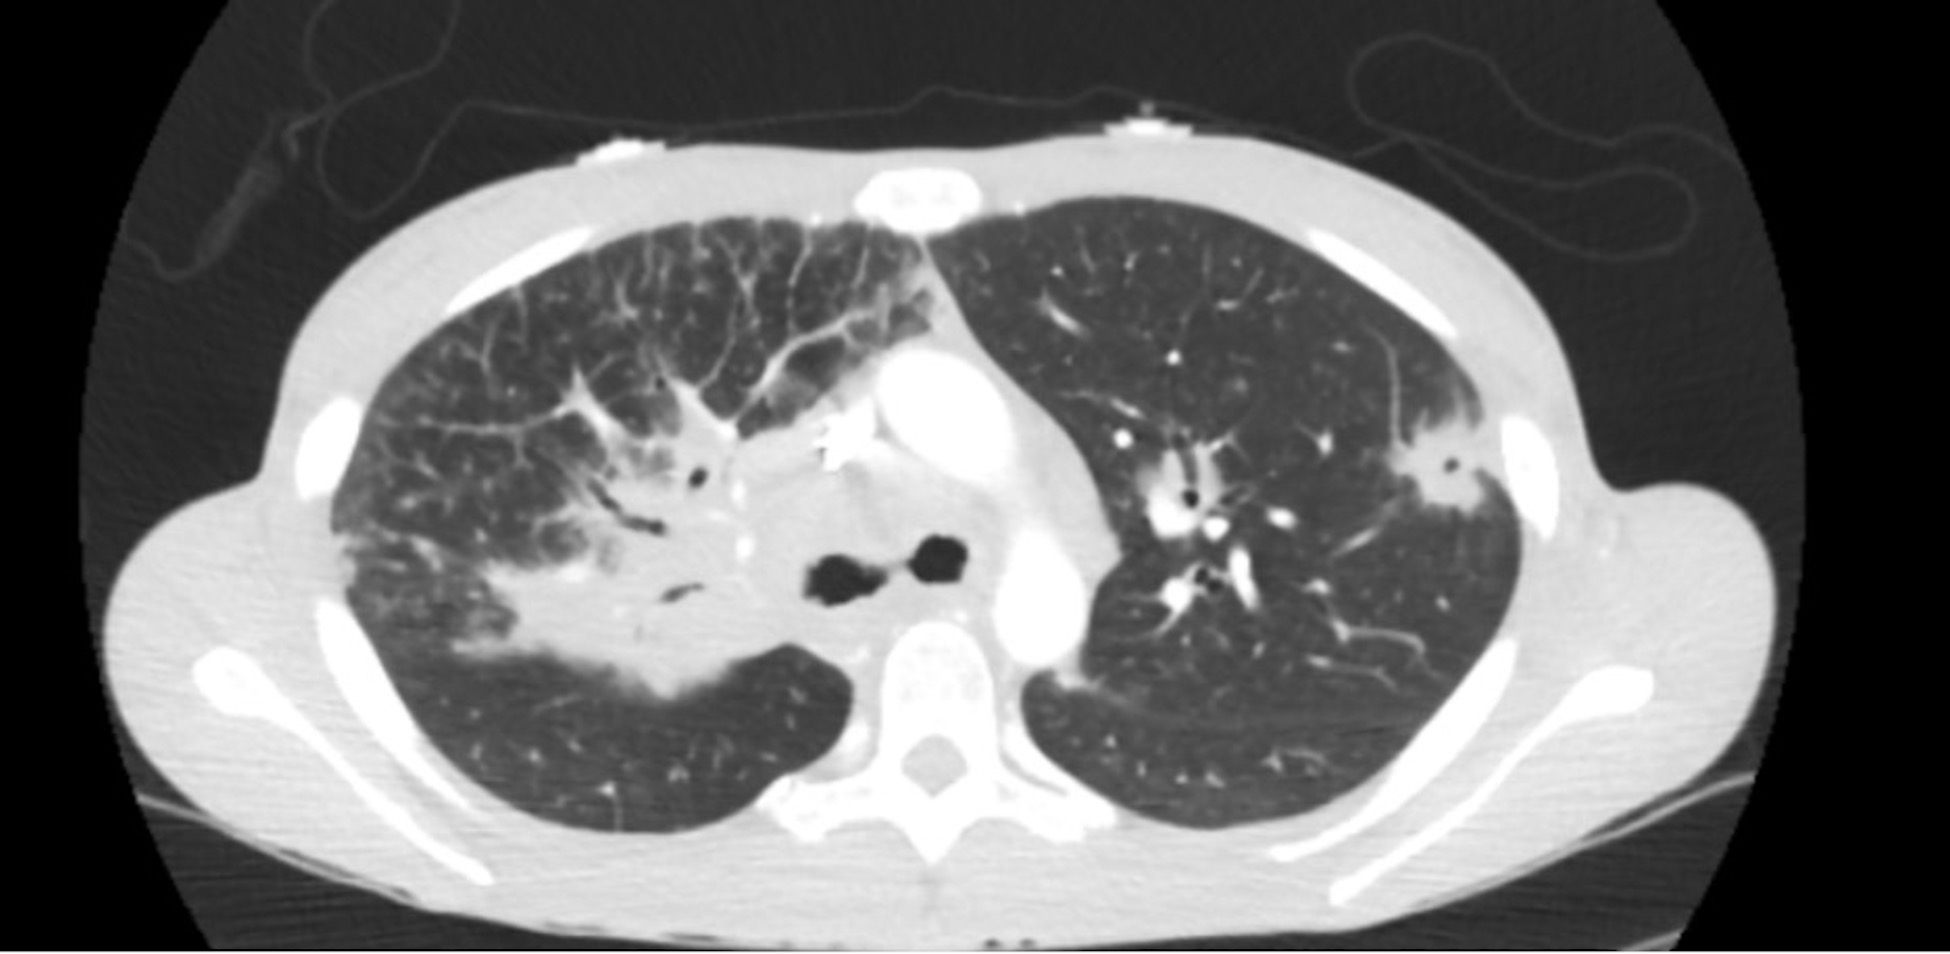

Sarcoidosis is a multisystem inflammatory disease characterized by non-caseating granulomas, primarily affecting the lungs but also involving other organs such as the skin, eyes, and heart.1 Due to its variable presentation, diagnosing sarcoidosis in the emergency department (ED) can be challenging. We report a case of a 28-year-old African American female presenting with acute dyspnea on exertion, significant weight loss, and multiple cutaneous nodules. Her diagnostic workup revealed hypercalcemia, diffuse pulmonary nodules, and extensive lymphadenopathy on imaging. Biopsy of her eyelid lesions confirmed non-caseating granulomas, leading to a diagnosis of sarcoidosis. She was initiated on high-dose steroids and evaluated for further immunologic therapy. Sarcoidosis presents a diagnostic challenge due to its nonspecific symptoms, often mimicking more common conditions.2 Early recognition in the ED is critical to prevent disease progression. This case underscores the importance of considering sarcoidosis in patients with unexplained systemic symptoms and highlights the need for a multidisciplinary approach to management.